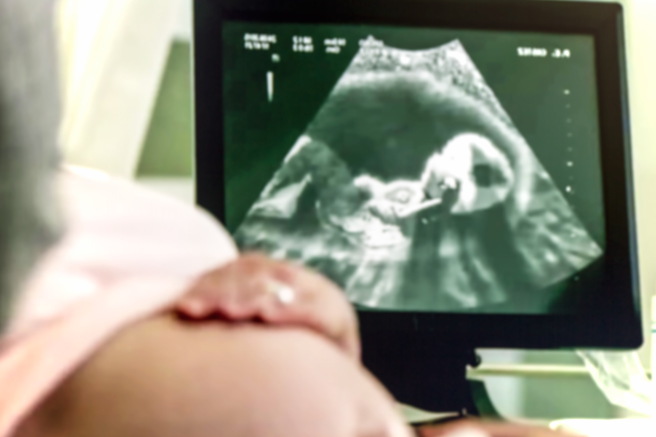

李浩偉改幫婦人做陰道超音波,確認避孕器位置,透過畫面發現避孕器卡在子宮頸跟子宮交接處,且是寶寶在體內用腳不斷地踢,把避孕器踢到很低的位置,才導致婦人有出血狀況。

李浩偉評估婦人已懷胎5個月,做流產手術會有風險,若取出避孕器恐會讓羊水破裂,影響到胎兒,因此婦人決定生下孩子,懷孕期間也不取出避孕器。李浩偉說,婦人最後在足月的時候生產,避孕器也跟著寶寶一起「生出來」,寶寶頑強的生命力,也讓李浩偉驚呼連連。